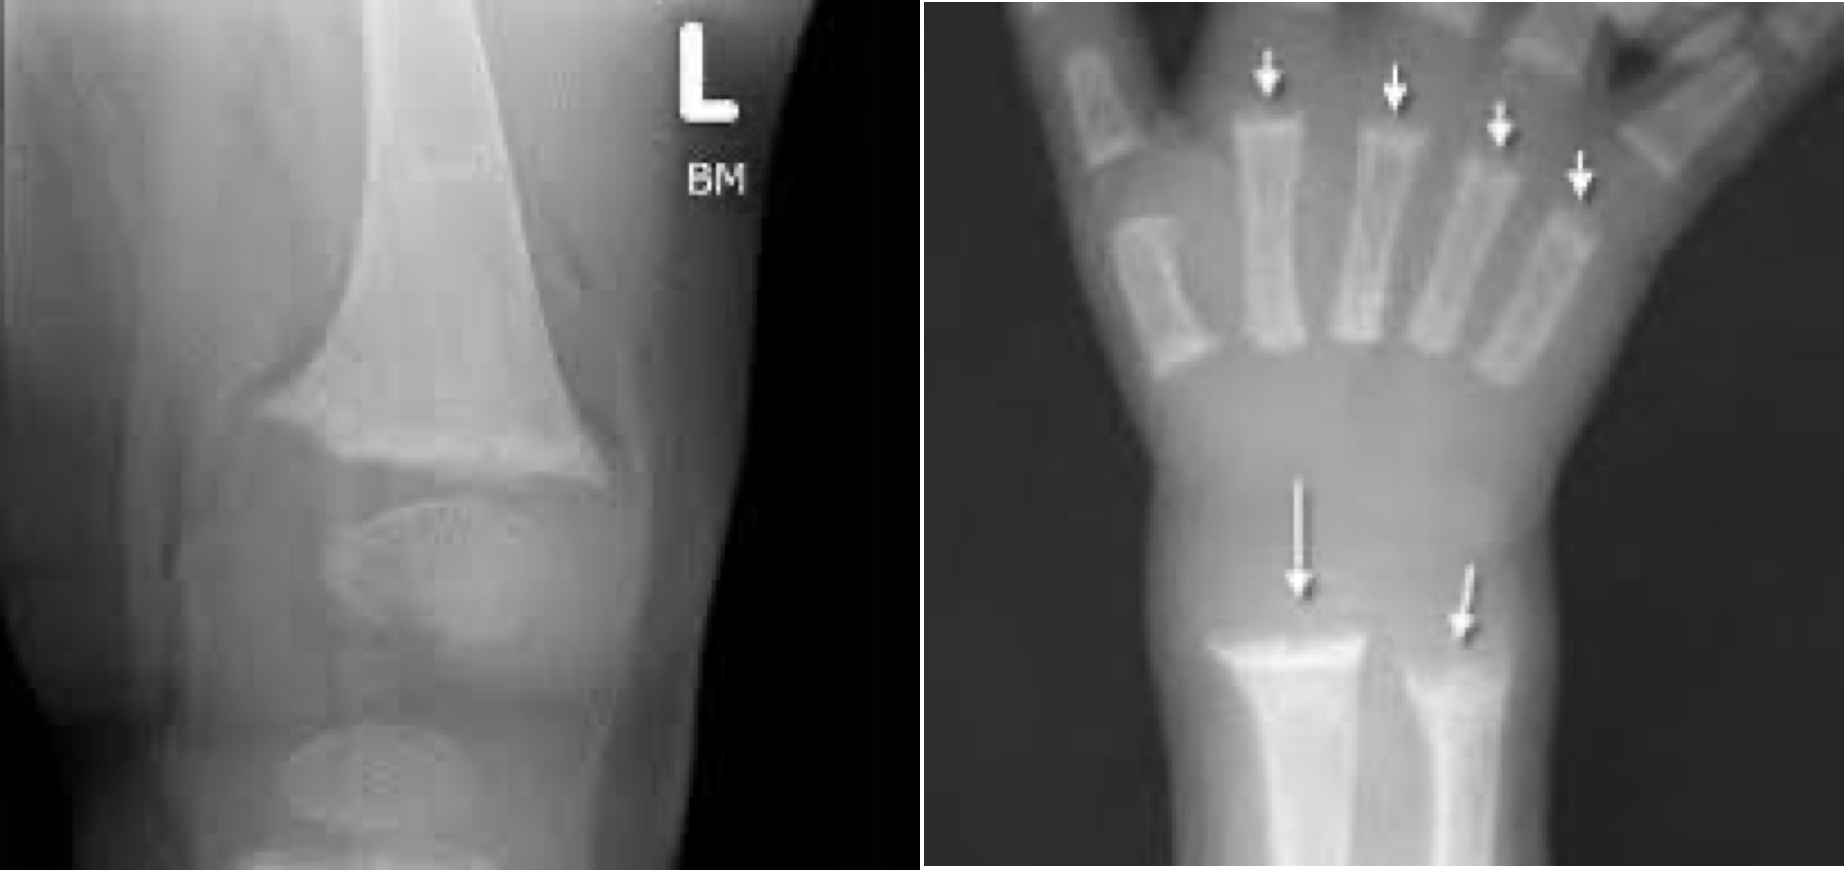

구루병 (Rickets)

• 임상양상

• 두개골 연화

• 구루병 염주 (rachitic rosary)

• metaphyseal cupping/widening (“champagne glass deformity”)

• 혈액검사 시 ALP 상승, 25-OH-D 감소, 저인산혈증